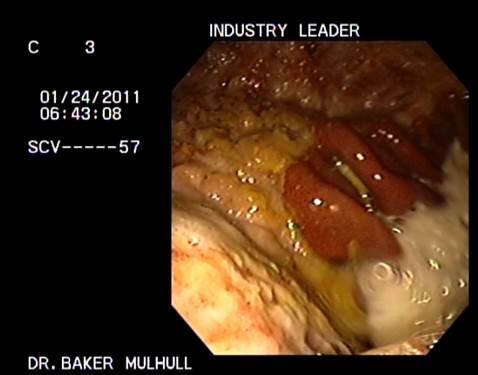

I treated my mare with THE GastroPlus as well. And if I decide to buy the horse I'm trying out, I will be ordering it again. Ask WyomingBarrelRacer for the study's pictures. Tells a thousand words.

~BINGO~ - 2015-11-11 9:46 AM

Here are the pictures

(cato 1.png)

(Cato 2.png)

(Indian 1.jpg)

(Indian 2.jpg)

(Industry 1.jpg)

(Industry 2.jpg)